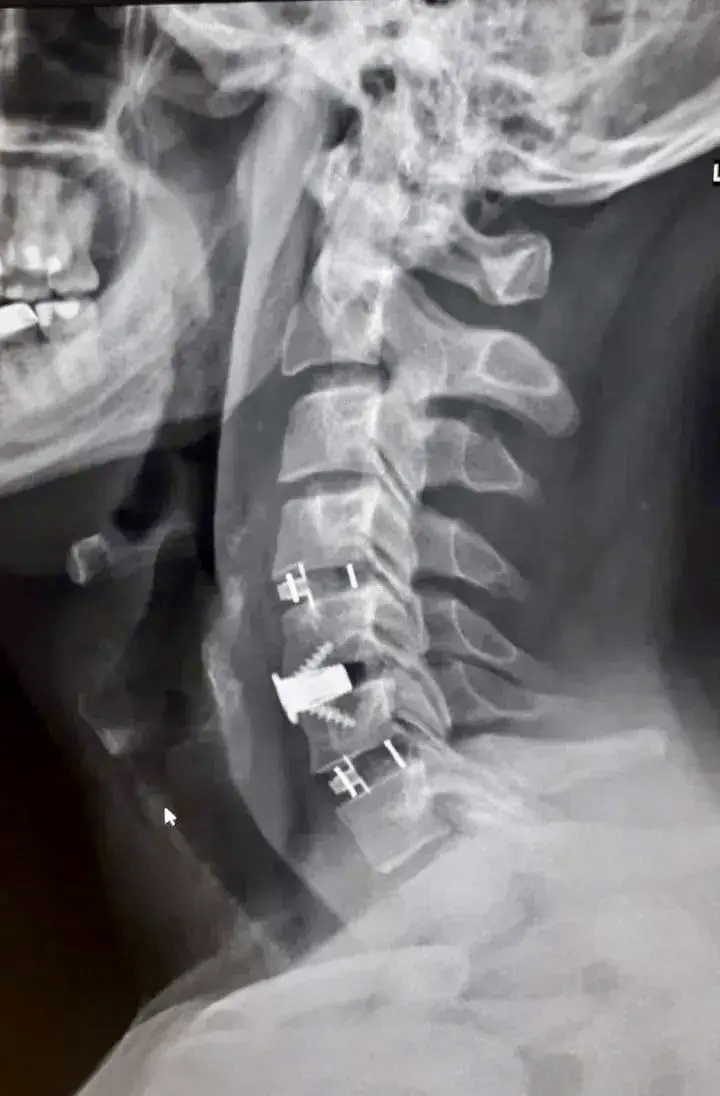

После подготовки мужчине провели операцию с применением комбинированной техники. Бригаду врачей возглавил заведующий нейрохирургическим отделением Павел Юров. Специалисты устранили сдавление и одновременно зафиксировали позвоночник, укрепив его титановыми конструкциями.